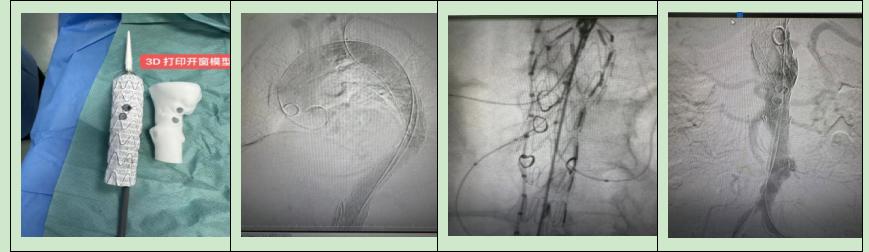

心血管内科介入团队成功应用3D打印开窗技术完成首例胸腹主动脉覆膜支架手术及内脏动脉血运重建术

近日,心血管内科介入团队为一例74岁患者成功应用3D打印开窗技术完成首例胸腹主动脉覆膜支架手术及内脏动脉血运重建术。该例手术的成功开展,标志着我院心脏介入水平在大血管领域又一重大医疗技术突破,填补了崇州地区该项技术的空白,对进一步提升我院介入医疗技术水平具有重要意义。

胸腹主动脉瘤被称为腹腔内的不定时“炸弹”,随时有发生破裂出血风险,死亡率极高。我院心血管内科吴军主任高度重视患者病情,联合肝胆外科、呼吸科、麻醉科、放射科等科室进行多学科讨论、分析后指出,患者有行介入手术治疗指征,但该患者手术难点在于胸腹主动脉瘤及壁内血肿、溃疡病变累及广泛,在行支架植入的同时应保证相应分支血管支配的内脏血供,经详细讨论后最终制定了应用3D打印开窗技术行胸腹主动脉覆膜支架术及内脏动脉血运重建的手术方案,该项手术难度大,风险高,家属同意手术,经过充分的术前准备,在麻醉科全麻护航下,历经5个多小时紧张又精准的手术操作后,胸腹主动脉覆膜支架植入成功、贴壁好,造影显示左锁骨下动脉、腹腔干、肠系膜上动脉、双肾动脉显影佳,手术顺利结束。术后患者转危为安,上腹痛症状缓解,在医护精心照料下,患者术后恢复良好,目前已康复出院。